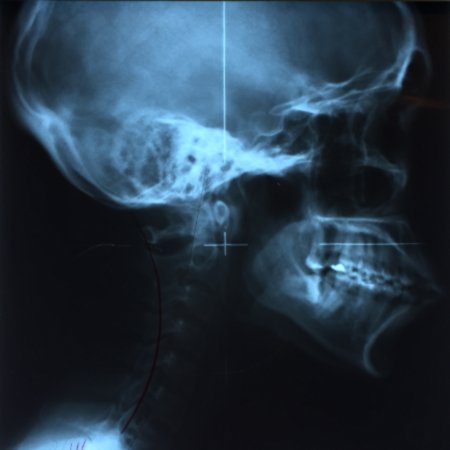

If it’s your first time to go to an upper cervical chiropractor, you’ll need an average of 8 to 12 visits, then the doctor will re-assess you for lifetime treatment. The first session involves a general assessment of your health, habits, and posture, followed by three x-rays (from the side, front, and top of head and neck) specific to the practice of upper cervical chiropractic. This is usually the longest session. The doctor will then study your x-rays, posture, and result of the initial consultation, and based on all these will determine if you need an atlas or spine adjustment on your next visit.